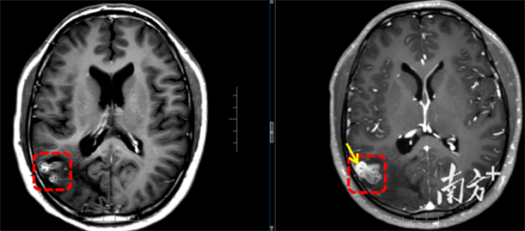

该院神经外八科二区副主任陈俊喜和主治医师王艮波接诊后,对比患者历次头部影像发现,病灶不仅位置移动,还呈现“隧道征”,高度指向脑裂头蚴病。后续血清检查结果也提示裂头蚴抗体阳性。

“除近期的癫痫大发作,患者此前频繁出现视野闪光、画面感,也是癫痫发作引起的。”陈俊喜解释,从影像来看,虫体已从大脑深部爬至表层,正是手术取出的好时机。很快,他带领团队为患者进行裂头蚴捉取手术,成功取出一条长约18cm的活虫。